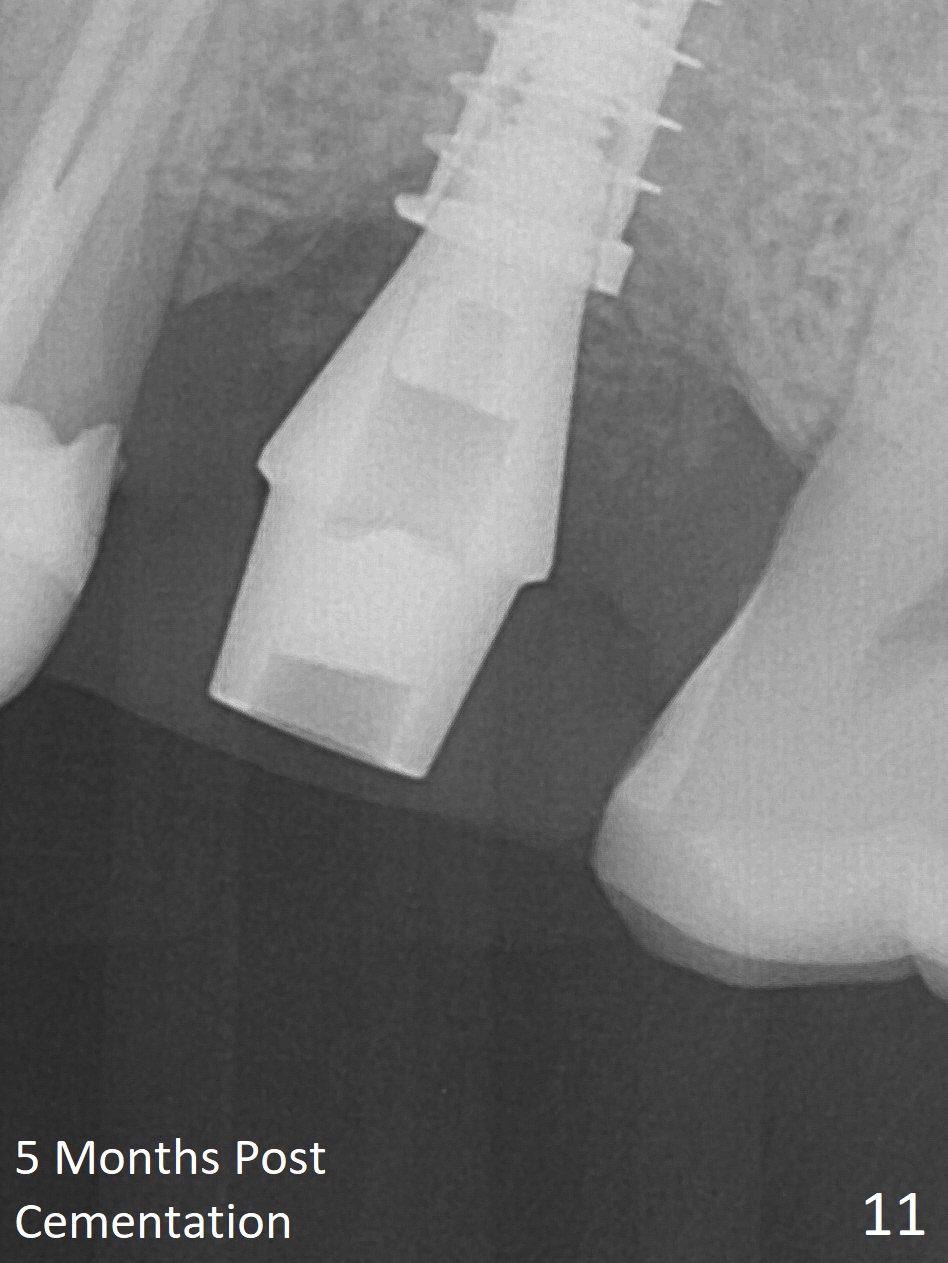

After extraction of the distobuccal residual root of the tooth #14 (Fig.1 arrow), the gingiva around the socket does not look like the keratinized one (Fig.2 *). An osteotomy through the distobuccal socket would seem too buccal for immediate implant. The palatal gingiva feels too tough to be stretched. An incision is made (Fig.3 dashed line); with elevation, the thick flap is transferred buccally (curved arrow). An osteotomy is initiated in the palatal bone with 1.5 mm drill, followed by Magic Expanders until 4.3 mm for 11 mm (Fig.4,5). Following Magic Drill 3.8x13 mm, the sinus membrane is found to be perforated. The latter is repaired with Osteogen plug. A 4.5x9 mm IBS implant is placed with 50 Ncm (Fig.6). Osteogen plug and allograft (Fig.7 *) are inserted into the remaining distobuccal socket (reduced after bone expansion). When a 5.5x4(4) mm abutment is placed, the transferred flap appears to be adapted to the distobuccal defect (Fig.8 *). Later one suture is placed for fixation. After provisional insertion, periodontal dressing is applied. Nine days postop, the periodontal dressing dislodges. When the loose provisional is removed for recementation, the flap seem to have healed (Fig.9 *). The gingiva heals around the abutment 5 months postop (Fig.9); the distal socket appears to heal while the bone graft remains at the crest (Fig.11,12). When #30 develops buccal abscess, the patient masticates on the left, leading to loss of composite at #13 (Fig.14); in fact the abutment at #14 is incompletely seated.